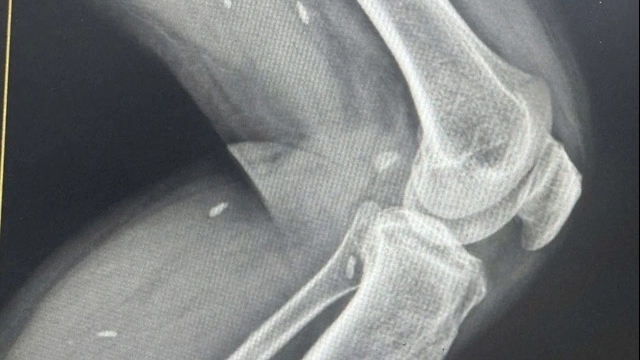

![]() |

Hội nghị cũng nghe các tham luận chuyên đề của Khoa Ngoại – Gây mê hồi sức về phát triển kỹ thuật chuyên môn và Phòng Dân số – Truyền thông, Giáo dục sức khỏe về nâng cao hiệu quả công tác truyền thông y tế tại cộng đồng.